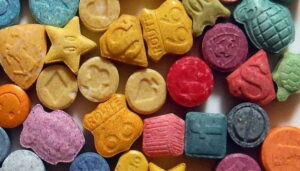

Sanitat

Èxtasi, de droga de discoteca a fer-se servir a la consulta dels psicòlegs?

Èxtasi, de droga de discoteca a fer-se servir a la consulta dels psicòlegs?

Èxtasi, de droga de discoteca a fer-se servir a la consulta dels psicòlegs?